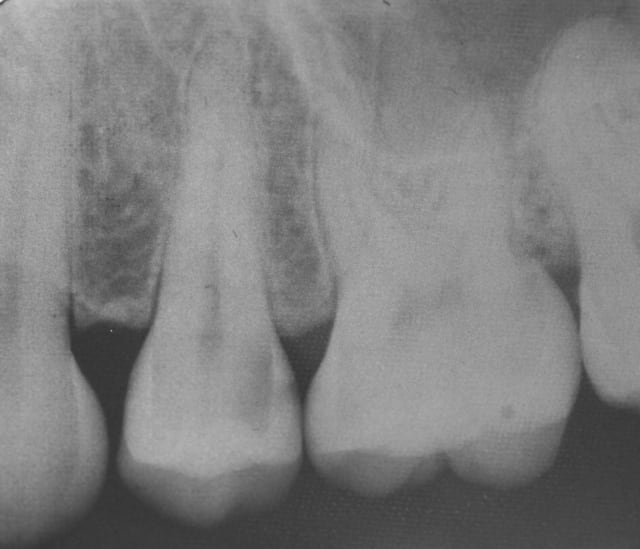

Un petit onlay du dimanche dernier qui m'a fait plaisir. A souligner le travail du prothésiste, content de son boulot après avoir vu les photos.

Pour Sethef: la digue (medium) ne m'a pas gêné, mais le premier clamp que j'ai voulu mettre remontait partiellement sur la limite.

Petite question, par curiosité: la cavité a l'air profonde sous la gencive, non?

La cavité d'accès pour une dévit est insuffisante , la dent est vivante . La limite de la cavité est sus gingivale .

Dent vitale. Il y avait un compo OD et le pan V a lâcher. Limite supra-gingivale.